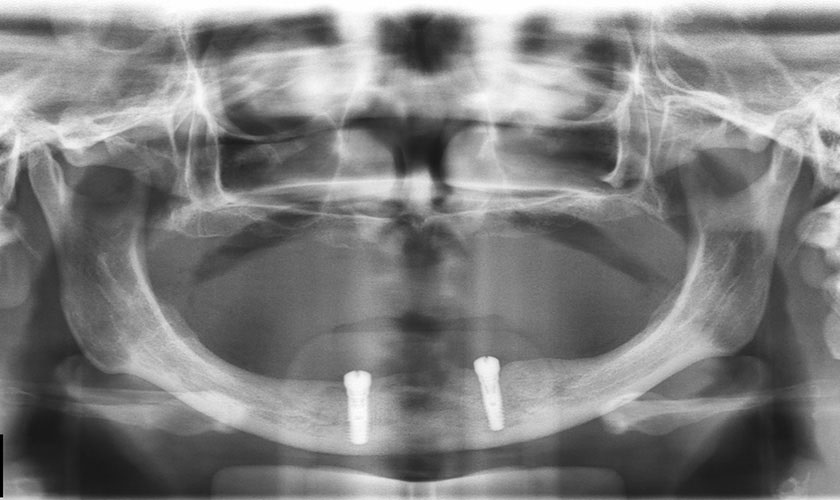

Thiếu răng bẩm sinh gây ra tình trạng tiêu xương hàm

Sau khi thăm khám và khảo sát trên phim X-quang, TS-BS Võ Văn Nhân cho biết: “Trường hợp của bệnh nhân Nguyễn Ngọc Hạnh vô cùng đặc biệt. Ở hàm trên, do không có răng nên hoàn toàn không có xương ổ răng, đồng thời xương nền hàm trên cũng cực kỳ mỏng. Để giải quyết tình huống này, cấy Implant xương gò má(*) là giải pháp sau cùng. Trên thiết kế Implant cho thấy, Implant chỉ còn khoảng 1 mm là xâm phạm vào ổ mắt, hố thái dương, vì vậy, chỉ một sai lệch nhỏ cũng có thể gây ra biến chứng nghiêm trọng.

Trong khi đó, ở hàm dưới, xương hàm bị tiêu trầm trọng, mỏng dần theo chiều ngoài trong, đỉnh sóng hàm gần sát thần kinh hàm dưới. Do đó, hàm dưới cũng cần phải cấy Implant cực kỳ chính xác, nếu không Implant sẽ dễ dàng lệch ra khỏi vị trí và bị sai hướng. Việc lệch ra ngoài hay vào trong cũng sẽ gây biến chứng nguy hiểm như: giảm thị lực, tổn thương ổ mắt, chấn thương cơ thái dương, hạn chế há miệng,… đồng thời trụ Implant vì vậy mà không thể tồn tại lâu dài.